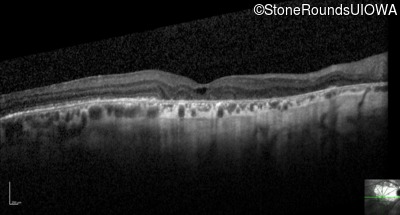

Optical Coherence Tomography - Right - 20/25 -2

Exemplar / OCT Stack